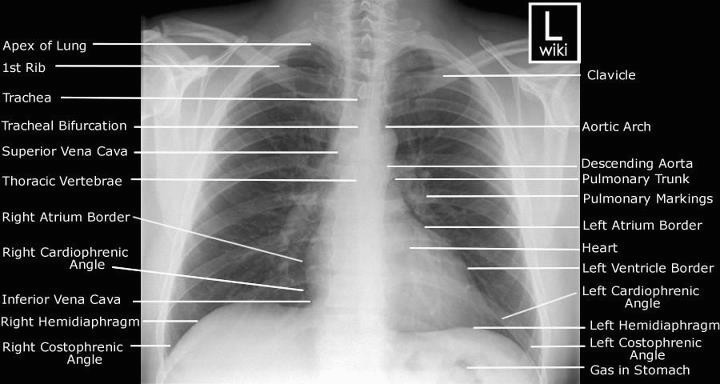

Pneumonia